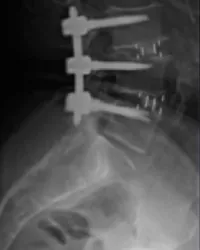

- Instabilités et malformations de la colonne : spondylolyse, spondylolisthésis dégénératif, fracture vertébrale, tassements vertébraux, malformations congénitales (sauf scolioses)…